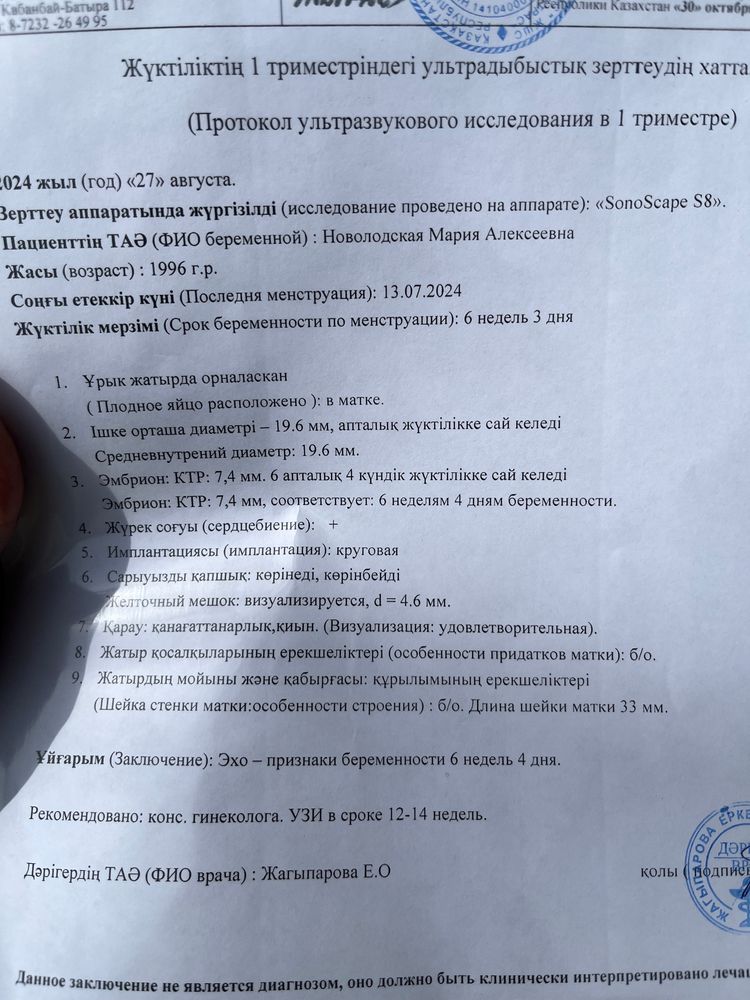

Татьяна , вы не представляете как я рада) особенно после вчерашнего узи где не увидели малыша и поставили кучу диагнозов